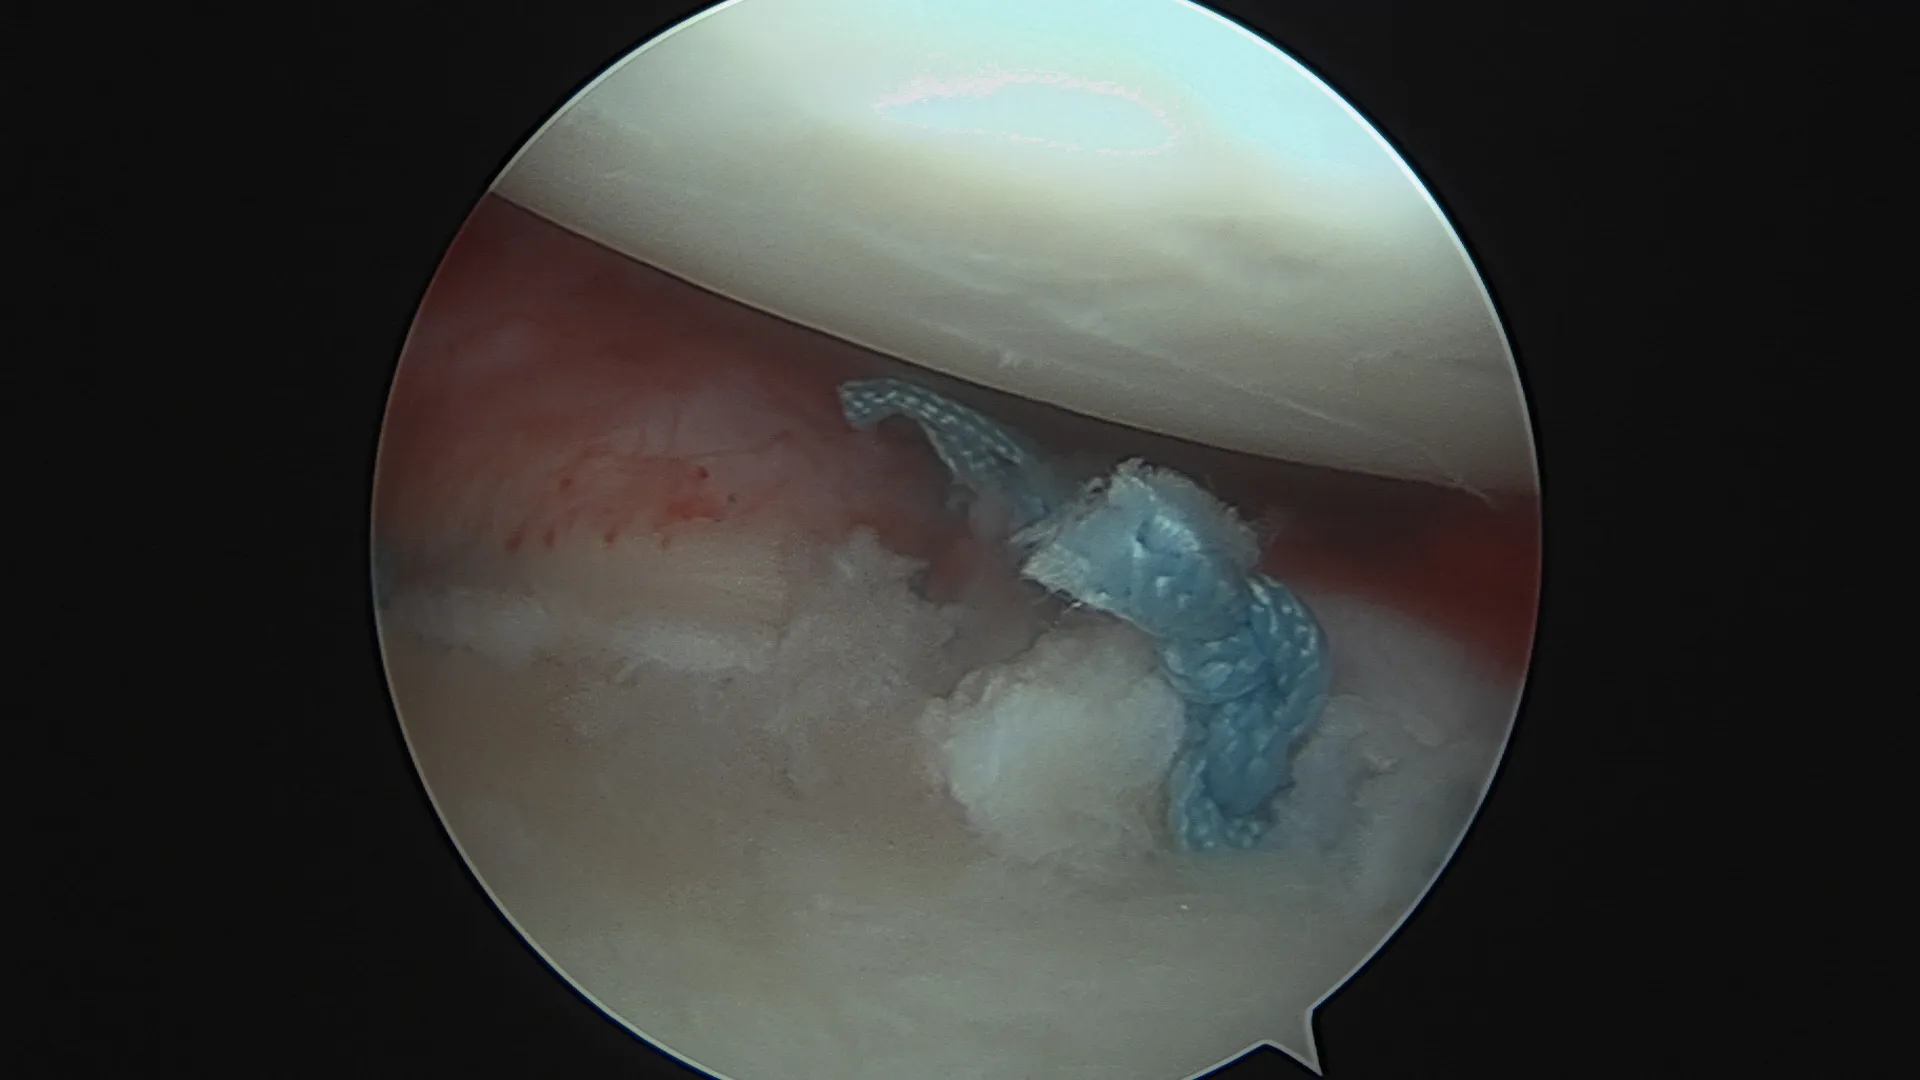

La lésion de HillSachs sous arthroscopie

Lors d'un épisode de luxation, la tête humérale venant heurter violemment la partie antéro-inférieure de la Glène, elle peut provoquer une fracture du rebord osseux de celle-ci. Lorsque la tête humérale vient s'incarcérer en regard de la glène, Elle peut également s'écraser et se déformer de façon irréversible à la manière d'une balle de ping-pong que l'on écraserait avec le doigt.

Lorsque les déformation osseuse sont importantes les techniques arthroscopiques ne suffisent pas à stabiliser l'épaule. La technique la plus appropriée est alors la réalisation d'une butée coracoïdienne. L'association d'une technique arthroscopique de réparation du bourrelet , d'une rétention capsulo-ligamentaire et un comblement de l'encoche de Hill-sachs peut être une alternative dans certains cas.